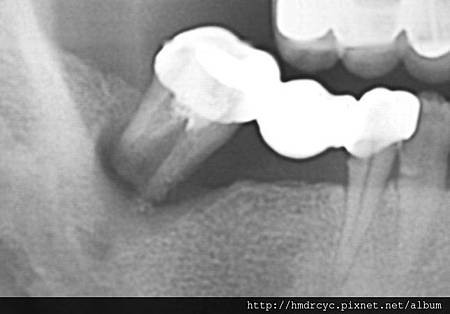

根管化膿是原本神經管裡的組織感染

因為上面有牙套 所以就往牙根尖方向蔓延

這會發生在沒有先做根管治療的牙齒

以及根管治療不完全的牙齒

解決方案必須考慮牙套拆除

重新根管治療 甚至牙根尖手術去除膿包

不然有時膿包繼續擴大

會感染到隔壁牙齒甚至形成囊腫